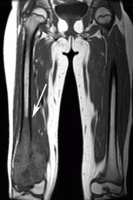

This is an MRI image of the thighs of a person who has osteosarcoma. The arrow points to the diseased area in the leg; the other leg appears to be unaffected.